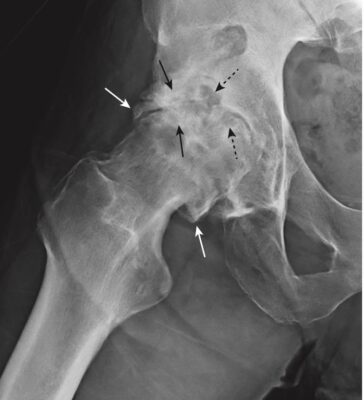

Hình 4. Thoái hoá khớp. Các dấu hiệu nhận biết của bệnh thoái hóa khớp được minh hoạ ở khớp háng phải của bệnh nhân này. Có sự tạo gai xương ở rìa khớp (mũi tên trắng đặc), đặc xương dưới sụn (mũi tên đen đặc) và hình thành các nang dưới sụn (mũi tên đen chấm).

Hình 7. Thoái hóa khớp thứ phát ở khớp háng phải. Có sự khác biệt rõ rệt giữa hai khớp háng: trong khi háng bên phải bị thoái hóa khớp nặng (mũi tên đen) thì khớp háng bên trái tương đối bình thường (mũi tên trắng). Bệnh nhân này bị trượt chỏm xương đùi (SCFE) bên phải và chưa từng được chăm sóc điều trị.